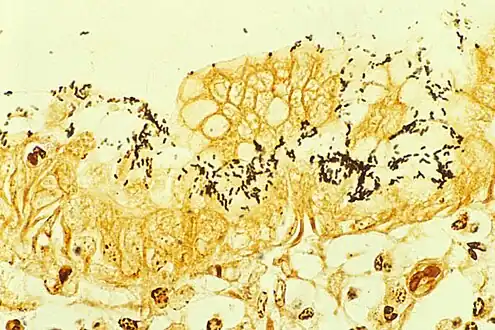

| Immunohistochemical staining of H. pylori (brown) from a gastric biopsy | |